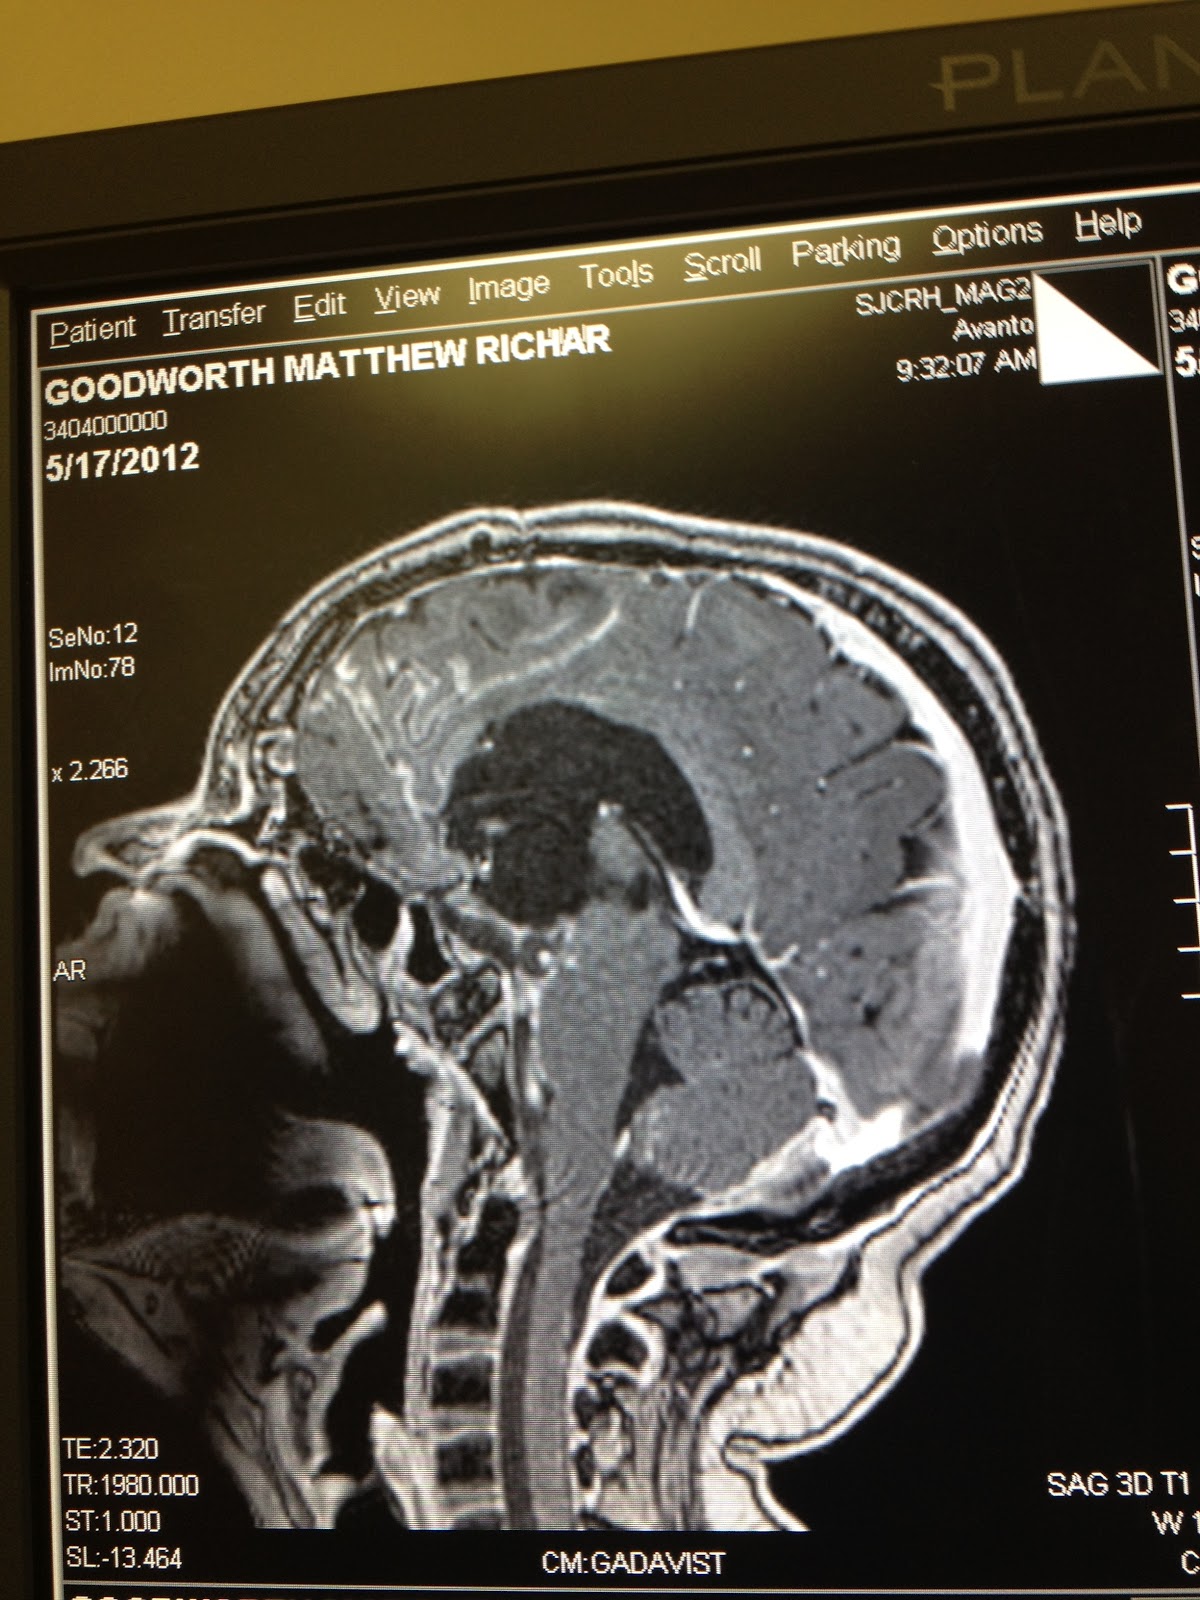

A picture is worth a thousand words, so I want to show you what research is doing to save my son.  This first scan shows his brain in November 2010.  Despite 3 years of treatment including 3 surgeries, almost 2 years of chemotherapy, and radiation, the tumor had grown larger than it had ever been.  This is a side view of Matt's head - notice his nose and face on the left of the scan.  The big white blob in the middle of the black space in the center is tumor.  All of the white snakey tendrils you see through the brain is also tumor that has spread.

This is the same side view of the tumor, taken 10 days ago when we were at St.Jude.

Here is a view looking down on his head from the top.  Again, the white blob in the center should not be there.

And here is the view from our last scans.

In this case, a picture is truly worth a thousand words.  :)